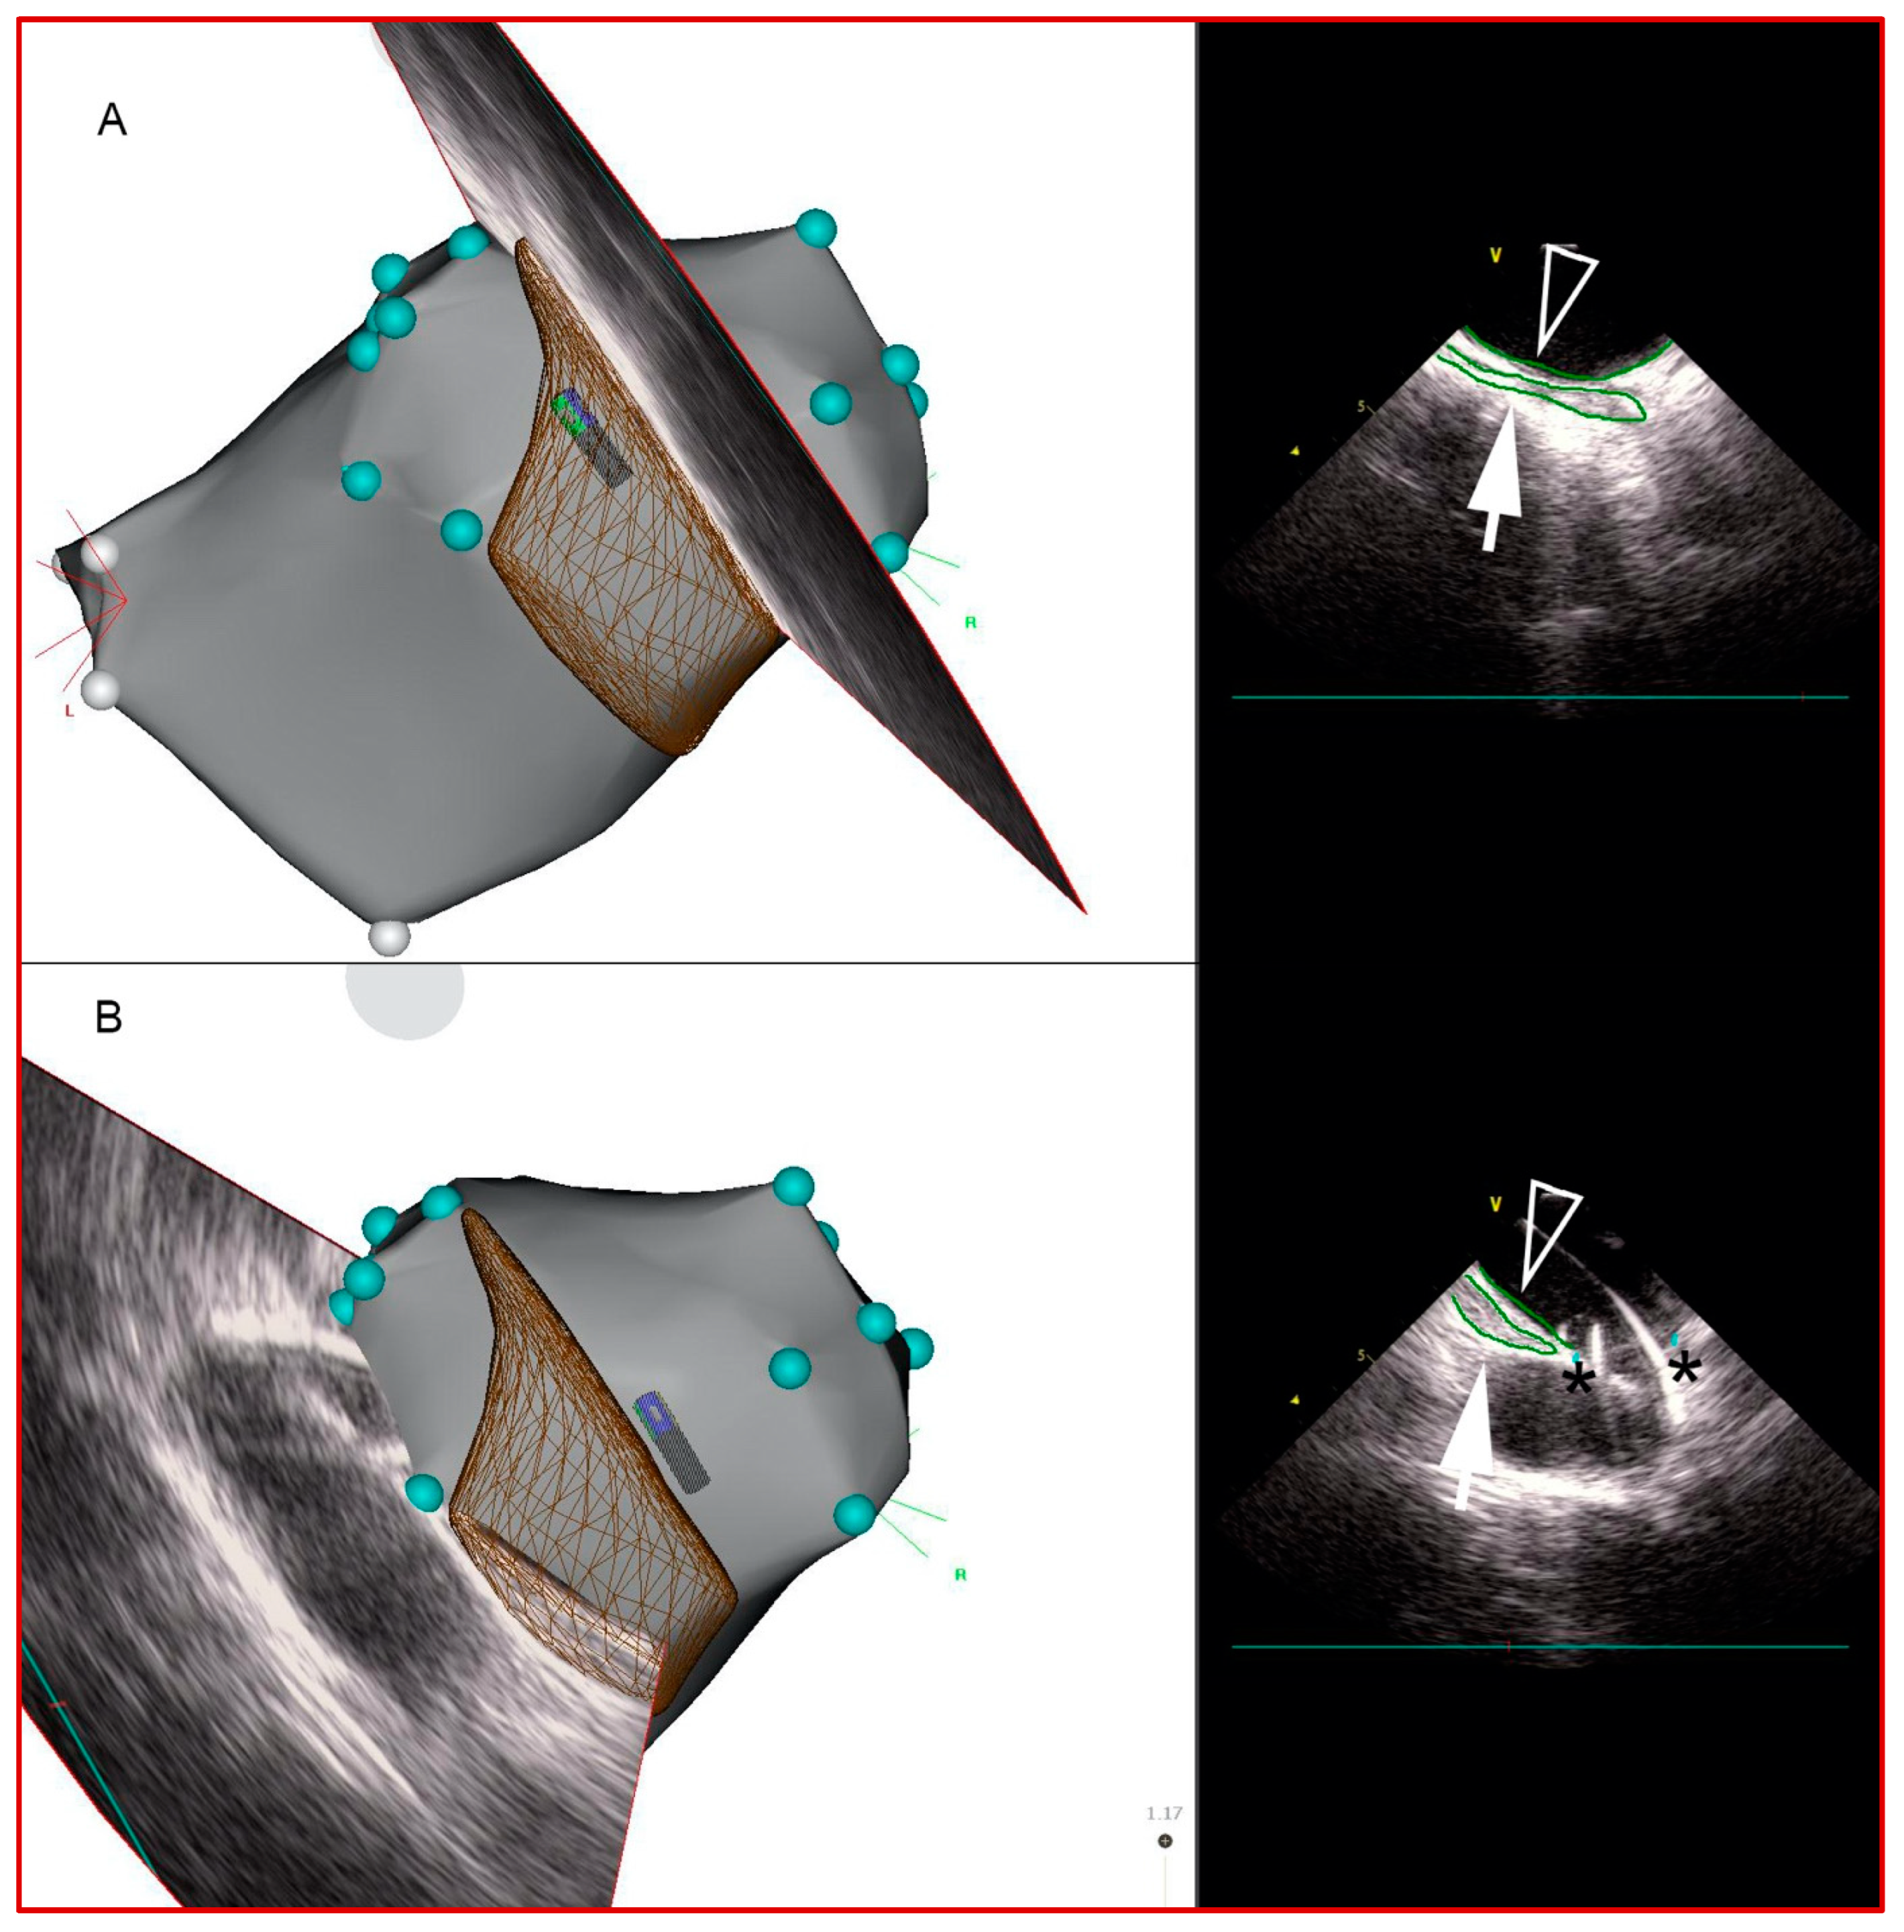

Figure 2.

Sequential intracardiac echocardiography (ICE)-derived 2D images of esophagus on CARTO. Esophageal borders (green contours) were traced to create its 3-dimensional course over the LA posterior wall. Panels (A,B). Medial (rightward) and lateral (leftward) esophagus borders, respectively. In panel (B), ICE view, the guidewire is seen going into left inferior PV. Closed arrows: esophageal contours; open arrows: LA posterior wall contours; asterisks: PV ostia.